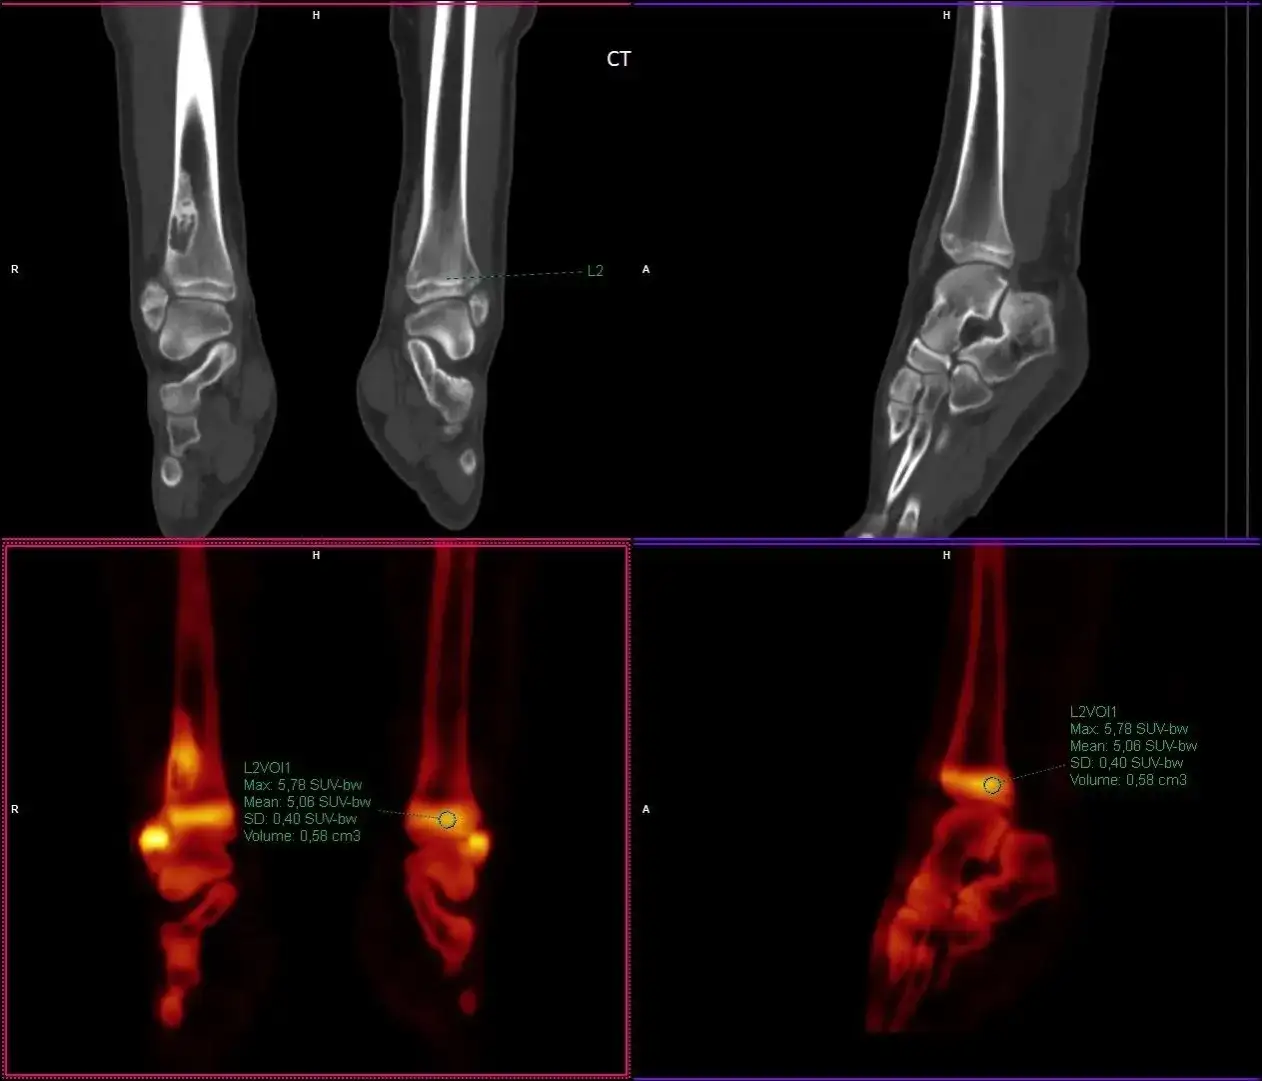

SUVmax to wskaźnik, który określa maksymalną wartość Standardized Uptake Value (SUV) dla voksela o najwyższej liczbie zliczeń w wybranym obszarze zainteresowania. Jest on wyznaczany podczas badań obrazowych, takich jak PET/CT lub SPECT/CT. Dzięki SUVmax lekarze mogą uzyskać informacje o najwyższej intensywności wychwytu radiofarmaceutyku w badanej tkance. To sprawia, że SUVmax jest niezwykle ważnym narzędziem w diagnostyce onkologicznej, pozwalającym na lepsze zrozumienie charakterystyki metabolicznej nowotworów.Wartość SUVmax jest użyteczna w ocenie stopnia zaawansowania choroby oraz w monitorowaniu odpowiedzi na leczenie. Pomimo że obliczenie SUVmax jest stosunkowo proste i nie zależy od subiektywnej oceny lekarza, należy pamiętać, że nie reprezentuje on wartości aktywności metabolicznej całego guza. W związku z tym, interpretacja wyników wymaga uwzględnienia dodatkowych czynników, takich jak metoda rekonstrukcji obrazu oraz poziom szumu, które mogą wpływać na ostateczne wyniki.

Aby obliczyć SUVmax, należy zastosować odpowiednią formułę, która uwzględnia aktywność radiofarmaceutyku w badanej tkance oraz masę ciała pacjenta. Wzór na SUVmax wygląda następująco: SUV = (Aktywność w tkance) / (Aktywność we krwi x Masa ciała). Wyniki tego obliczenia dostarczają informacji o intensywności wychwytu radiofarmaceutyku w danym obszarze, co może wskazywać na obecność nowotworu lub inne zmiany patologiczne.

Wyniki SUVmax mogą mieć różne wartości, które interpretowane są w kontekście klinicznym. Na przykład, wartości SUVmax powyżej określonego progu mogą sugerować obecność nowotworu, podczas gdy niższe wartości mogą wskazywać na tkankę zdrową. Kluczowe jest zrozumienie, że sama wartość SUVmax nie jest wystarczająca do postawienia diagnozy; zawsze powinna być analizowana w połączeniu z innymi wynikami badań oraz objawami klinicznymi pacjenta.